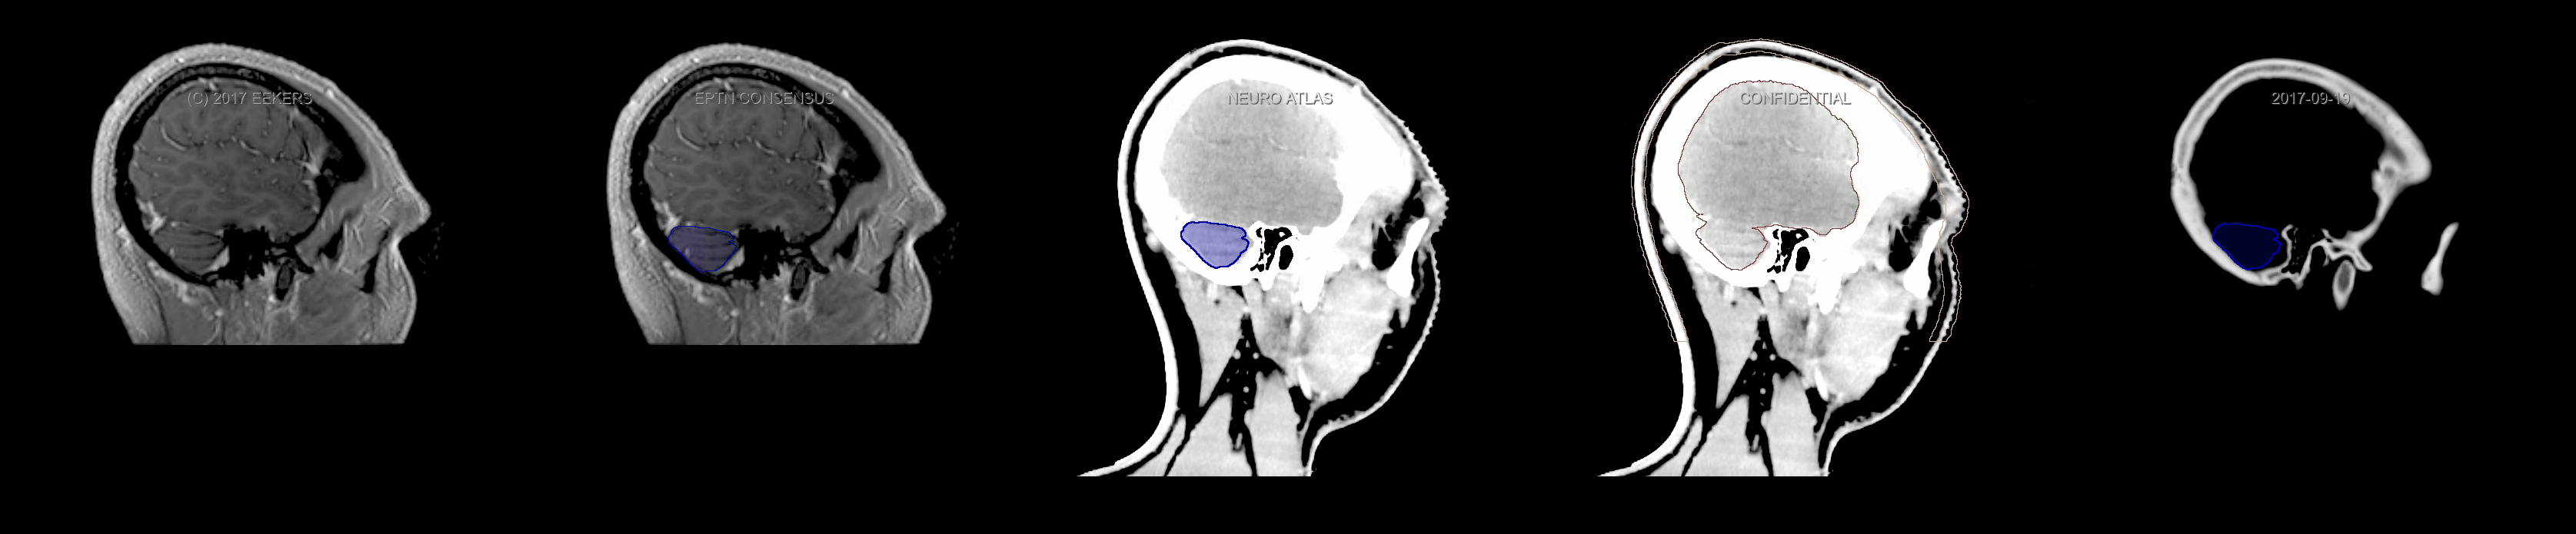

Three-dimensional delineation of the fifteen consensus OARs for neuro-oncology are shown on CT and 3 Tesla (3T) MR images (slice thickness 1 mm with intravenous contrast agent). All are presented in transversal, sagittal and coronal view.

From left to right: MR without structures, MR with structures, CT (WW/WL 120/40) with structures, CT (WW/WL 120/40) with Brain and Brainstem Surface, CT (WW/WL 1500/120)with structures